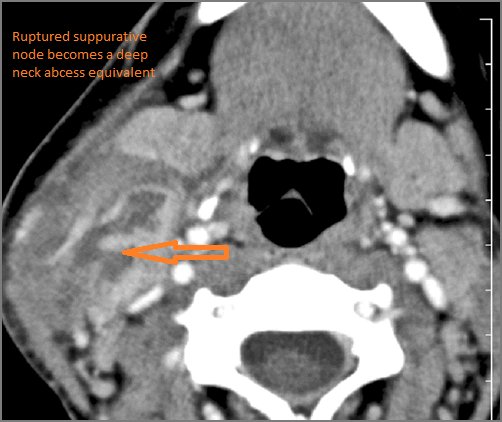

There is suppurative cervical lymphadenopathy. [Yes/No]

If there is suppurative cervical adenopathy the purulent material outside the lymph node(s) capsule(s). [Yes/No]